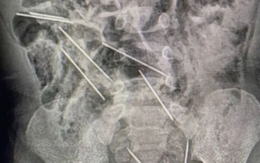

Cứu sống cậu bé 2 tuổi nuốt 8 cây kim tại Peru

Một cậu bé 2 tuổi tại Peru trong lúc đang chơi đã nuốt phải 8 cây kim y tế và may mắn được lấy hết kim ra khỏi bụng thành công.